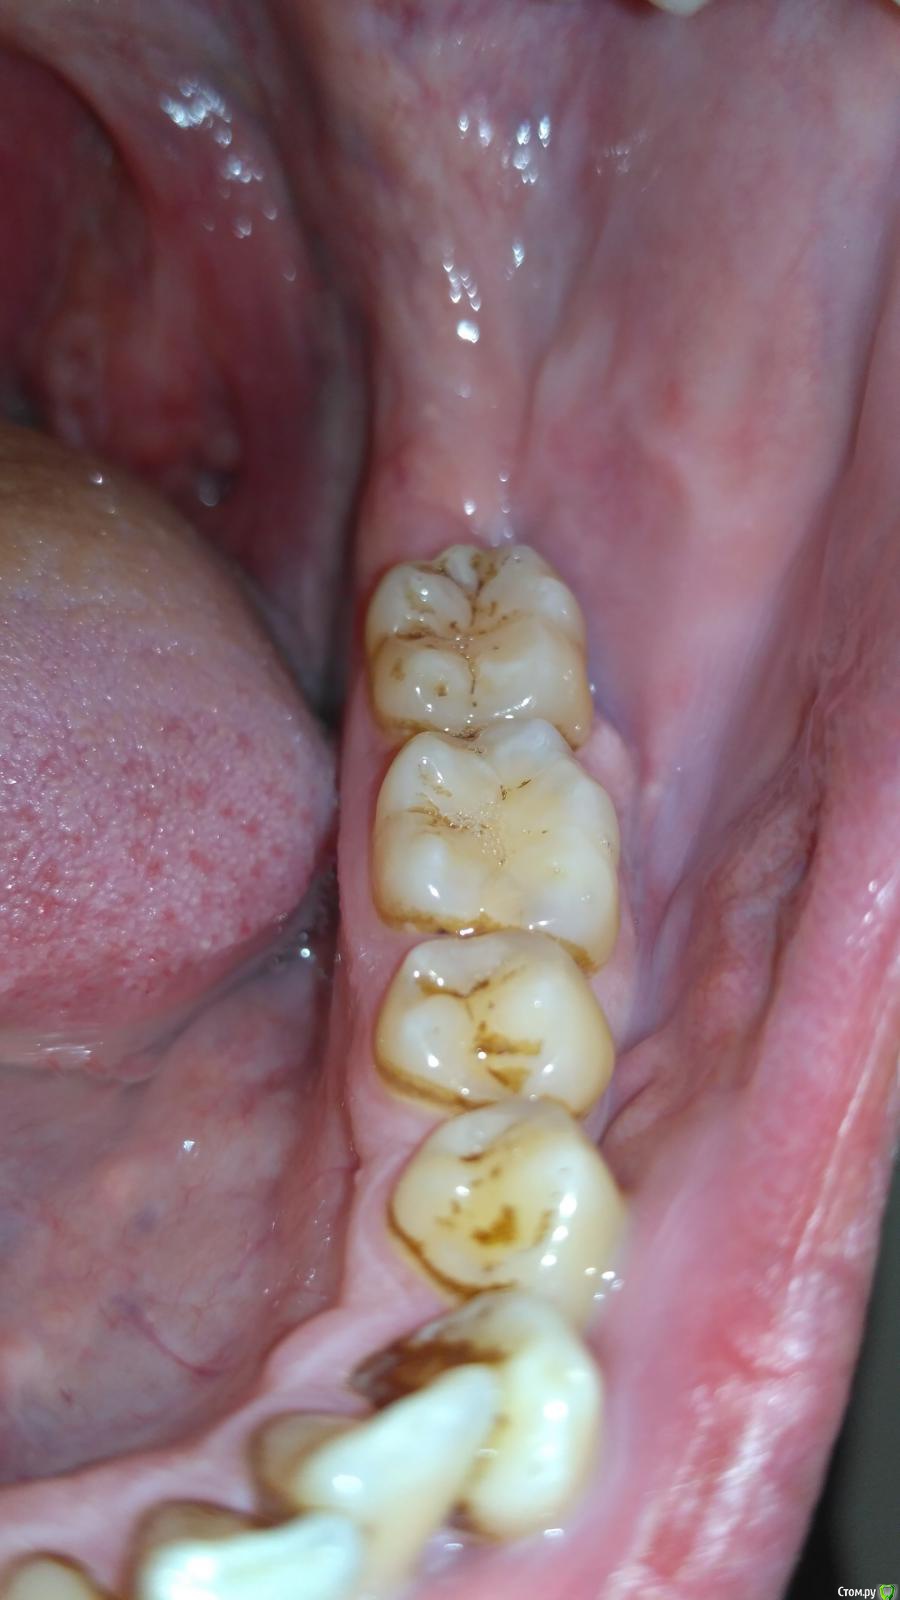

medbratec Опубликовано 10 октября, 2016 Автор Поделиться Опубликовано 10 октября, 2016 Пока полоскаю травами, на ночь Метрогил Дента. Стало меньше температурить.Завтра поеду на консультацию в отделение челюстно-лицевой хирургии.Как и обещал прикрепляю несколько фоток: Ссылка на комментарий

medbratec Опубликовано 13 октября, 2016 Автор Поделиться Опубликовано 13 октября, 2016 Я вас прекрасно понимаю. Был бы специалистом, то так сразу и сделал. Просто не знаю, что конкретно и под каким углом показывать. Сделал несколько скриншотов. Напишите, если они окажутся не слишком информативны. Ссылка на комментарий

medbratec Опубликовано 13 октября, 2016 Автор Поделиться Опубликовано 13 октября, 2016 Ссылка на комментарий